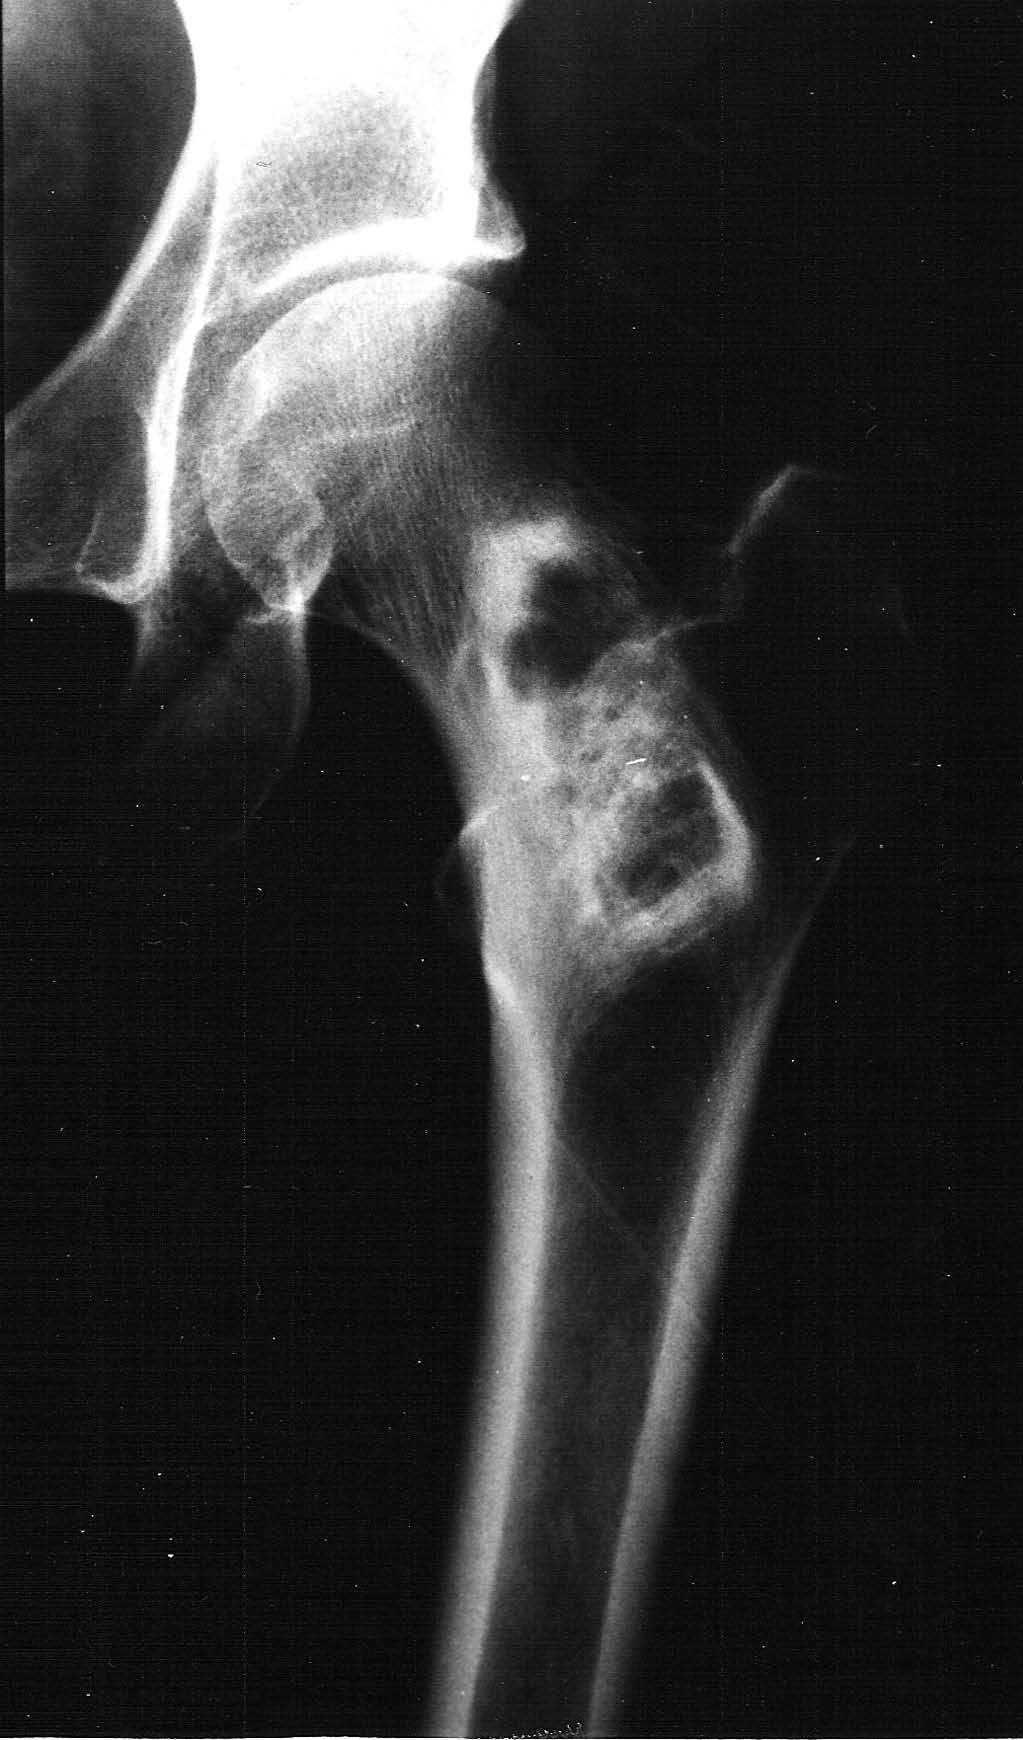

Mujer de 57 años que acude a nuestro hospital por un cuadro de dolor y claudicación en la extremidad inferior izquierda de varios meses de evolución. En la exploración clínica, no había cambios inflamatorios en las partes blandas ni sensación de masa, y las exploraciones neurológica y vascular fueron normales. En la radiografía anteroposterior de cadera izquierda (fig. 1) se visualizaba una lesión lítica en la metáfisis proximal del fémur. No se identificaba ningún tipo de matriz ósea en el interior, y estaba centrada y alineada en el eje longitudinal del hueso. La zona de transición era estrecha y el borde esclerótico, y contenía bandas o septos internos de esclerosis. No se visualizaba reacción perióstica, siendo de apariencia benigna. En este momento se incluyó dentro del diagnóstico diferencial la displasia fibrosa, el quiste óseo simple y el fibroma óseo, sin poder descartar que se tratase de un sarcoma de bajo grado.

Fig. 1.--Radiografía simple de fémur izquierdo. Lesión lítica metafisaria, sin matriz ósea interna y de borde esclerótico.